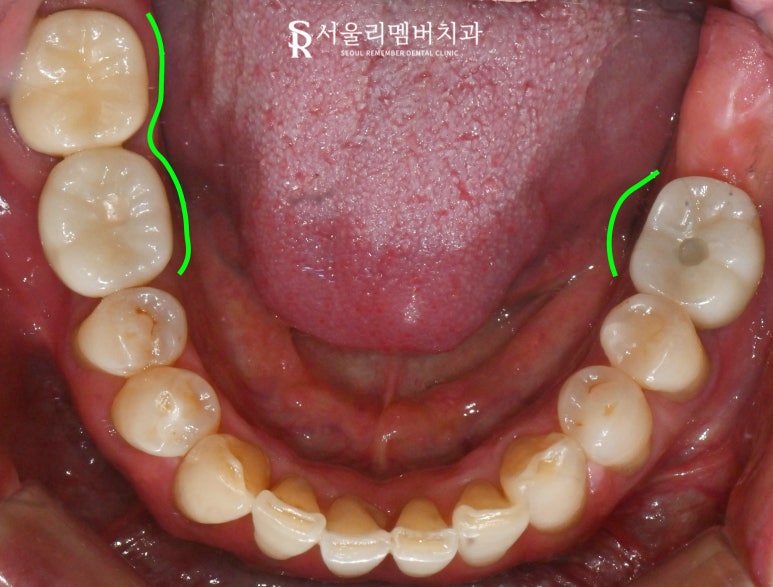

구강 현황을 확인하기 위해

먼저 검진과 엑스레이 촬영을 진행했습니다.

구강 검진:

치석과 치태, 그리고 치아 상실 문제

우선 낙성대 치과 에서 검진을 실시했을 때

구강 상태는 다음과 같았습니다.

(1) 상악

16번 이가 오래전에 빠지게 되어

치조골이 줄어든 모습이었으며,

17번은 위치가 불안정해져 있었습니다.

(2) 하악

46번이 없는 상태에서 47번은

배열과 위치가 좋지 않았고,

오래된 보철로 인해 기능이 저하된 것이었습니다.

하악 36번도 손실되었으며,

30번대 구치가 전반적으로 부재한 상황이었습니다.

(3) 전반적 문제

이를 다물었을 때 양측 교합이 불균형한 모습입니다.

또한 치석과 치태가 많이 껴 있어

치주 건강도 좋지 않았습니다.